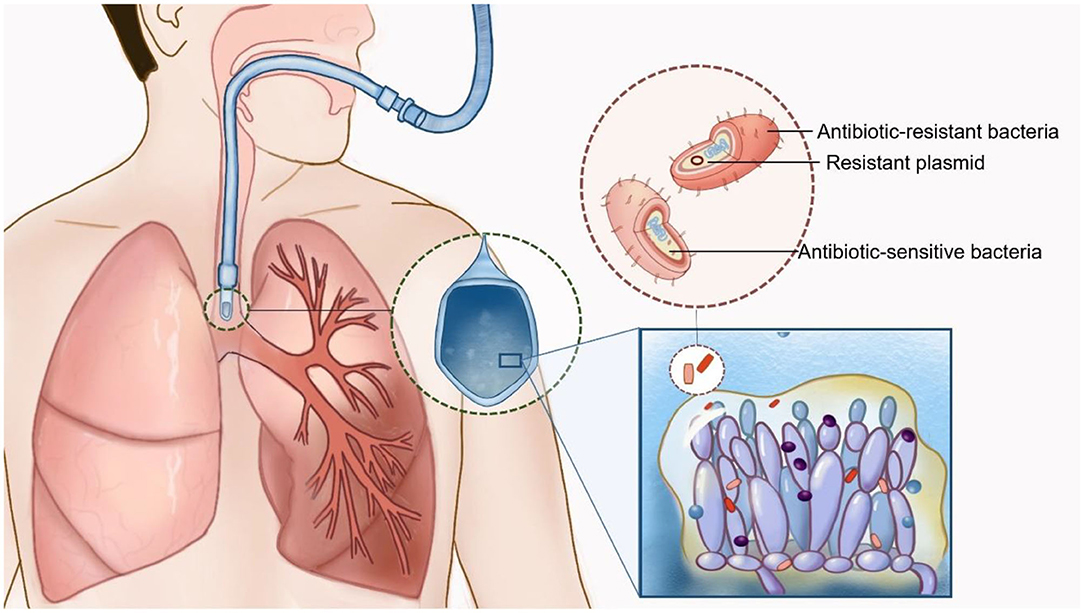

4 key things to know about lung infections caused by fungi discount, Frontiers Pathogenic Fungal Infection in the Lung discount, Fungal Pneumonia Overview Risk Factors Epidemiology of Fungal discount, Pulmonary aspergilloma Information Mount Sinai New York discount, 3 common types of lung fungus Vinmec discount, Fungal Lung Disease Makes World s Deadliest Bacteria Even Worse discount, Fungal infections of the lung in children Pediatric Radiology discount, World s first clinical guidelines for chronic fungal lung infections discount, Pulmonary fungal infection Imaging findings in immunocompetent discount, Frontiers Recent Advances in Fungal Infections From Lung discount, Fungal Pneumonia Overview Risk Factors Epidemiology of Fungal discount, Pulmonary fungal infection Imaging findings in immunocompetent discount, Is it TB or a fungal lung infection New life saving guidelines discount, Fungal pneumonia causes symptoms diagnosis treatment discount, COVID 19 associated pulmonary aspergillosis caused by aspergillus discount, Fungi are present in your lungs Faculty of Medicine UiB discount, Aspergillus Pneumonia Appears to Be Most Common Fungal Infection discount, CT image of lung with pulmonary Candida infection. There are many discount, A Schizophyllum commune fungus ball in a lung cancer cavity a discount, Fatal Fungal Lung infection affects TB recovered patients due to discount, Respiratory Mycoses Microbiology discount, Pulmonary fungal infection Imaging findings in immunocompetent discount, What is Aspergillosis Fungal Infections Symptoms Video discount, Blastomycosis Wikipedia discount, How nanoparticle drug inhalation helps fungal lung infections discount, Aspergillosis Types of Fungal Diseases Fungal Diseases CDC discount, Fungal pneumonia Wikipedia discount, Frontiers Candida Colonization in the Respiratory Tract What Is discount, How to fight fungal infection the path of yeast resistance discount, Pulmonary aspergilloma Information Mount Sinai New York discount, Fungal Infection Not Just Toenails Blueberry Therapeutics discount, Lung disease fungus grows here discount, Frontiers Case Report Invasive Fungal Infection and Daratumumab discount, A case report of fungal infection associated acute fibrinous and discount, Mice found able to ward off fungal lung infections by causing discount.

4 key things to know about lung infections caused by fungi discount, Frontiers Pathogenic Fungal Infection in the Lung discount, Fungal Pneumonia Overview Risk Factors Epidemiology of Fungal discount, Pulmonary aspergilloma Information Mount Sinai New York discount, 3 common types of lung fungus Vinmec discount, Fungal Lung Disease Makes World s Deadliest Bacteria Even Worse discount, Fungal infections of the lung in children Pediatric Radiology discount, World s first clinical guidelines for chronic fungal lung infections discount, Pulmonary fungal infection Imaging findings in immunocompetent discount, Frontiers Recent Advances in Fungal Infections From Lung discount, Fungal Pneumonia Overview Risk Factors Epidemiology of Fungal discount, Pulmonary fungal infection Imaging findings in immunocompetent discount, Is it TB or a fungal lung infection New life saving guidelines discount, Fungal pneumonia causes symptoms diagnosis treatment discount, COVID 19 associated pulmonary aspergillosis caused by aspergillus discount, Fungi are present in your lungs Faculty of Medicine UiB discount, Aspergillus Pneumonia Appears to Be Most Common Fungal Infection discount, CT image of lung with pulmonary Candida infection. There are many discount, A Schizophyllum commune fungus ball in a lung cancer cavity a discount, Fatal Fungal Lung infection affects TB recovered patients due to discount, Respiratory Mycoses Microbiology discount, Pulmonary fungal infection Imaging findings in immunocompetent discount, What is Aspergillosis Fungal Infections Symptoms Video discount, Blastomycosis Wikipedia discount, How nanoparticle drug inhalation helps fungal lung infections discount, Aspergillosis Types of Fungal Diseases Fungal Diseases CDC discount, Fungal pneumonia Wikipedia discount, Frontiers Candida Colonization in the Respiratory Tract What Is discount, How to fight fungal infection the path of yeast resistance discount, Pulmonary aspergilloma Information Mount Sinai New York discount, Fungal Infection Not Just Toenails Blueberry Therapeutics discount, Lung disease fungus grows here discount, Frontiers Case Report Invasive Fungal Infection and Daratumumab discount, A case report of fungal infection associated acute fibrinous and discount, Mice found able to ward off fungal lung infections by causing discount.